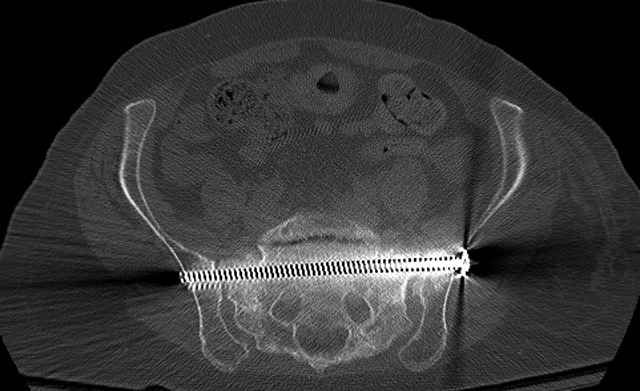

Here are a recent patient’s example slides...

Percutaneous Fixation

(B) Ramus-Retrograde

2 TransIliac-TransSacral

Upper Segment